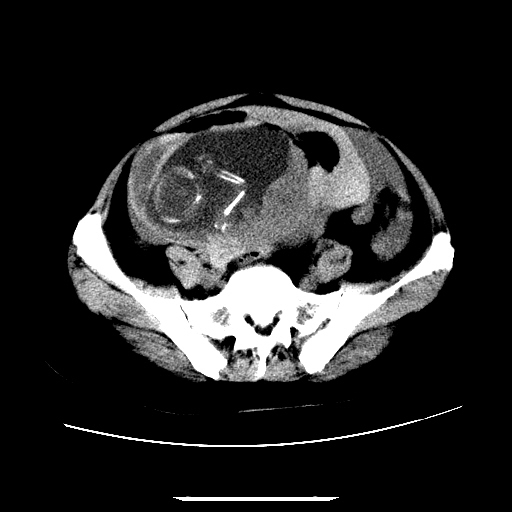

f,45y.怀孕4月晕倒,b超提示死胎,有手术结果,请展开讨论后明天告诉。

膈下-肠间隙内见气体密度影,子宫轮廓显示不清,宫腔-腹腔积液,首选考虑---子宫破裂出血。

1)宫腔妊娠。2)子宫破裂出血,腹腔及盆腔积血。

怀孕4个月晕倒,病史就这么简单?有没有腹痛呢?腹腔内有没有气体?窗宽太窄了脂肪组织与气体已不好分。如果有气体,那就是空腔脏器穿孔,如胃肠穿孔。如没有气体,就考虑子宫破裂或宫外孕破裂。正常怀孕子宫破裂很少见,有可能是宫外孕。极有可能是残角子宫怀孕破裂。腹腔怀孕破裂也有可能。

感谢同行们的高见。手术结果:子宫破裂出血。

我们的诊断是:腹、盆腔积液(考虑腹盆腔脏器破裂出血);宫腔妊娠。让人纳闷的是当时我们没有经验,现在回头看看分析:4月宫腔妊娠:1、洋膜囊不可能紧贴胎体这么小;2仔细看看子宫后壁肌层模糊不清;3腹、盆腔液体来源原因?4、45岁高龄妊娠有晕倒。由此可大胆诊断:宫腔妊娠子宫破裂出血。